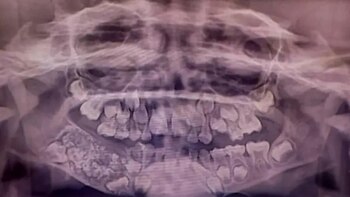

El increíble caso del niño al que le extrajeron 526 dientes en una sola cirugía

El menor, de 7 años, fue operado en Chennai, India, tras sufrir fuertes dolores e hinchazón en la mandíbula. Los profesionales hallaron una rara anomalía odontológica